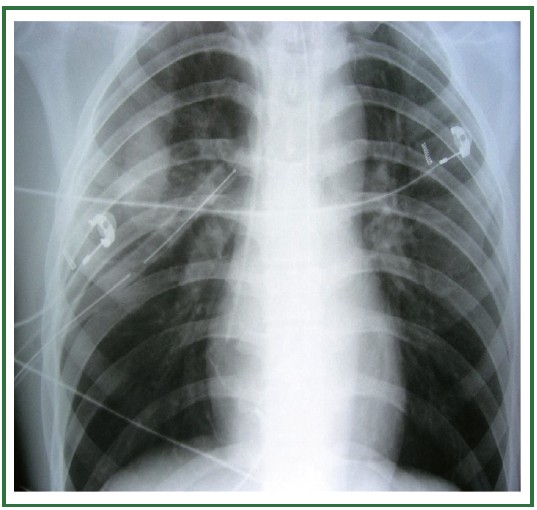

Second CXR for the case (post chest-tube insertion) found here:

(CXR source: http://jtd.amegroups.com/article/view/663/html)